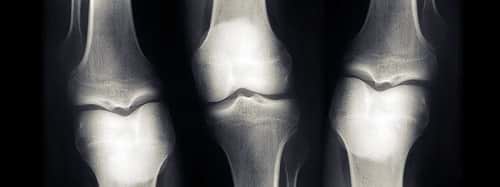

Neglecting our diet and lifestyle can make us susceptible to osteoporosis, which not only affects our quality of life but also restricts our mobility and causes pain. Osteoporosis weakens bones to the point that even a minor fall or stress can result in fractures. When osteoporosis sets in, the creation of new bone cannot keep up with the loss of old bone.

To address osteoporosis, it is essential to assess bone strength and density. The widely adopted method for this is dual-energy X-ray absorptiometry (DEXA) scan. DEXA scan helps determine bone health and the risk of fractures associated with osteoporosis. At Anup Institute of Orthopedics and Rehabilitation (AIOR) in Patna, we offer world-class DEXA scan services using the most advanced DEXA machine, a pioneering technology in Bihar.